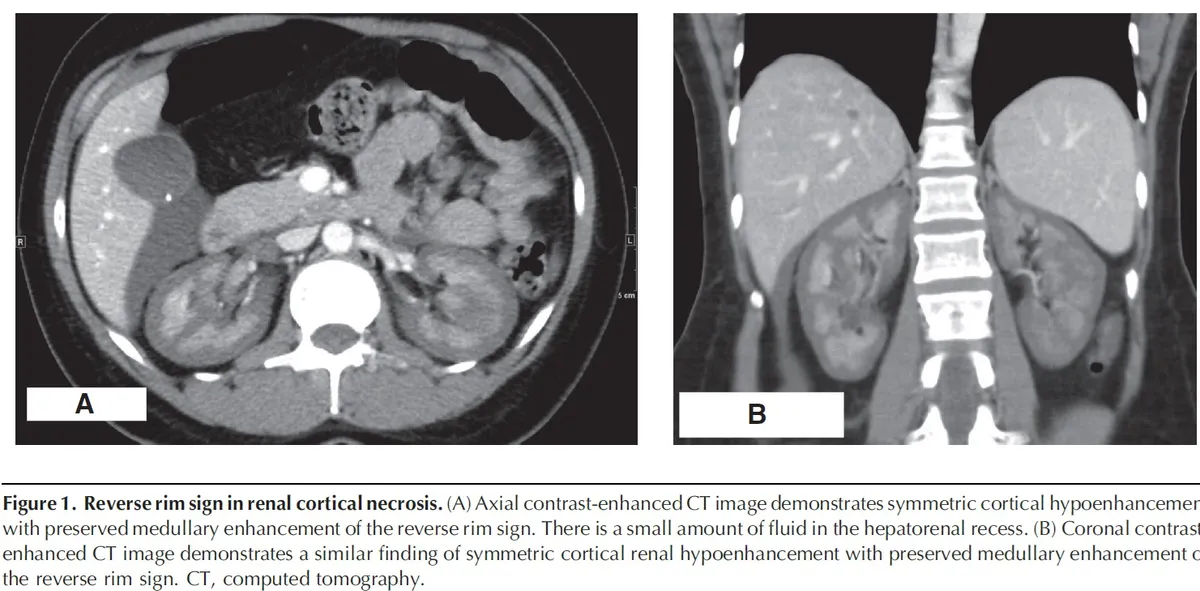

Nos dias seguintes, a creatinina sérica aumentou para 13 mg/dl, acompanhada de anúria. Realizado tomografia computadorizada de abdome (imagem da capa do post) que revelou sinais de necrose cortical renal (NCR), sinais de reversão renal (córtex hipodenso quando comparado a medula renal) com presença de um trombo na veia cava inferior e na veia gonadal direita. A paciente iniciou hemodiálise devido aos sintomas urêmicos e permaneceu dependente da diálise por cerca de dois meses. Após seis meses, a creatinina sérica caiu para 2,4 mg/dl, com um clearance de creatinina de 33 ml/min e proteinúria subnefrótica de 300 mg/d. A paciente continuo em tratamento conservador com diuréticos de alça em baixa dose e anticoagulação.

A NCR é uma forma grave e frequentemente irreversível de lesão renal isquêmica, resultante de uma redução prolongada da perfusão arterial renal. Esta condição é geralmente associada à CIVD e apresenta-se com início abrupto de oligúria ou anúria, algumas vezes acompanhada de hematúria macroscópica e dor no flanco. A TC com contraste mostrou a preservação da medula renal e a hipocaptação cortical (rim reverso), confirmando o diagnóstico de NCR.

3. Diagnóstico por Imagem: TC ou ressonância magnética (RM) são os exames de imagem de escolha para o diagnóstico preciso da NCR.